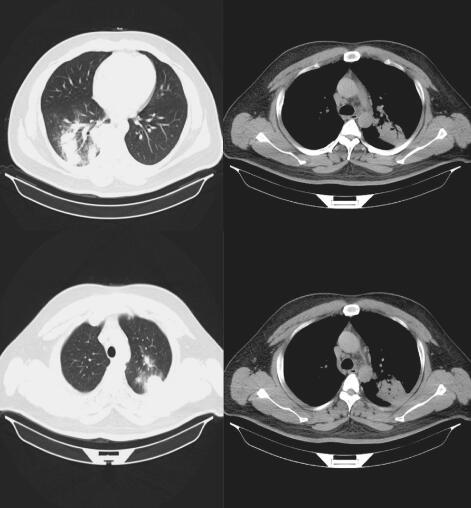

入院后完善相关检查,血常规示WBC 10.4×109,N% 80.9%,血气分析正常,肝肾功能、电解质、血糖未见明显异常,ANA、ENA阴性,P-ANCA弱阳性,PR3 20.19,C-ANCA阴性,MPO阴性,循环免疫复合物0.071↑;复查胸部CT,较外院末次检查继续进展(图1及图2的胸部CT表现),遂行支气管镜检查术;术中见左、右主支气管及各亚段支气管黏膜充血肿胀、管腔通畅、未见新生物,气管镜检查细菌、真菌和TB等病原学均阴性,行隐球菌乳胶凝集试验1∶320阳性,后行经皮肺穿刺活检病理结果是:送检组织未见正常肺组织结构,可见大量类上皮细胞及吞噬隐球菌孢子的异物巨细胞,伴淋巴细胞和巨细胞浸润,符合隐球菌感染表现。

图1 2014年12月5日胸部CT提示两肺多发实变影

图2 2014年12月15日胸部CT

两肺多发实变影,伴空腔样改变